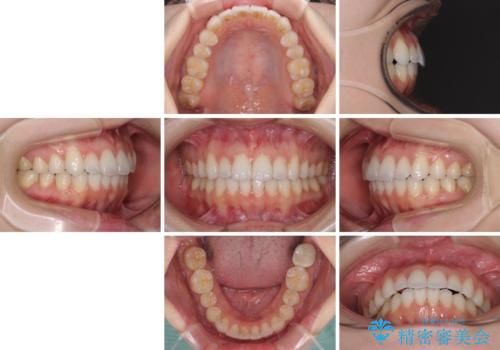

- 矯正治療の後戻りを気にして来院された患者様です。

後戻りは軽微でしたが、舌突出癖が認められ、初診時には上下前歯に舌がはまるスペースができていました。

舌突出癖の改善を行いながら、インビザライン・ライトにより矯正治療を行うこととしました。

舌突出癖の改善により上下前歯が接触するようになり、前歯でものを咬みきる必要のある食事がスムーズに行えるようになりました。